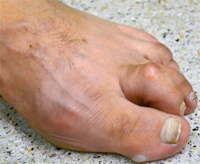

Claw Toe

The claw toe or hammer toe describes a deformity or curvature of the small toe. By increasing the shortening first digital flexor tendon in the middle joint, then the extensor tendon in the base joint, there is a curvature of the toe. In this way, pain and cornifications occur under the ball of the foot, and painful pressure points on the interphalangeal joints (corns). This deformity can usually only be corrected surgically. By an extension of the extensor tendon and solution of the joint capsule, together with a stiffening means in the toe joint, the toe is straightened permanently. The pressure points and relieves pain.